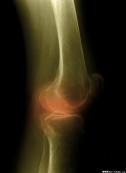

臨床上多見的增生性骨關(guān)節(jié)病可有多個(gè)名稱,包括退化性關(guān)節(jié)炎、骨關(guān)節(jié)炎及肥大性關(guān)節(jié)炎等。本病是由于關(guān)節(jié)退行性變,以致關(guān)節(jié)軟骨被破壞而引起的慢性關(guān)節(jié)病。

- 常見癥狀:關(guān)節(jié)疼痛、腫脹、活動(dòng)受限、僵硬感、勞累后、受涼后加重